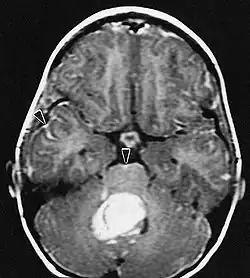

Les patients souffrent d'une variété de symptômes caractéristiques d'une lésion massive focale ou multifocale. L'IRM montre généralement des tumeurs avec un rehaussement de contraste homogène au sein de la substance blanche périventriculaire profonde. La multifocalité et le rehaussement inhomogène sont typiques des patients dont le système immunitaire est affaibli. L'analyse du lymphome du SNC est extrêmement importante dans le diagnostic différentiel de la néoplasie cérébrale. Il est à noter que l'administration de corticoïdes peut entraîner la disparition complète du rehaussement, rendant difficile le diagnostic des lésions. Par conséquent, si un lymphome du SNC doit être pris en compte dans le diagnostic différentiel, les corticoïdes doivent être évités à moins que l'effet de masse ne provoque un problème grave et immédiat chez le patient.